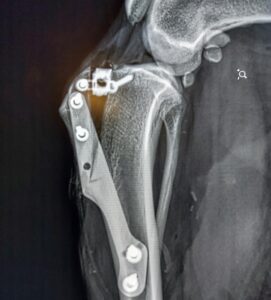

Tematem dzisiejszych warsztatów jest technika TTA (Tibial Tuberosity Advancement), czyli operacyjne przesunięcie guzowatości piszczelowej. Jest to jedna metod leczenia zerwania więzadła krzyżowego przedniego u psów.

Podczas warsztatów wykorzystaliśmy klatki TTA klasyczne.